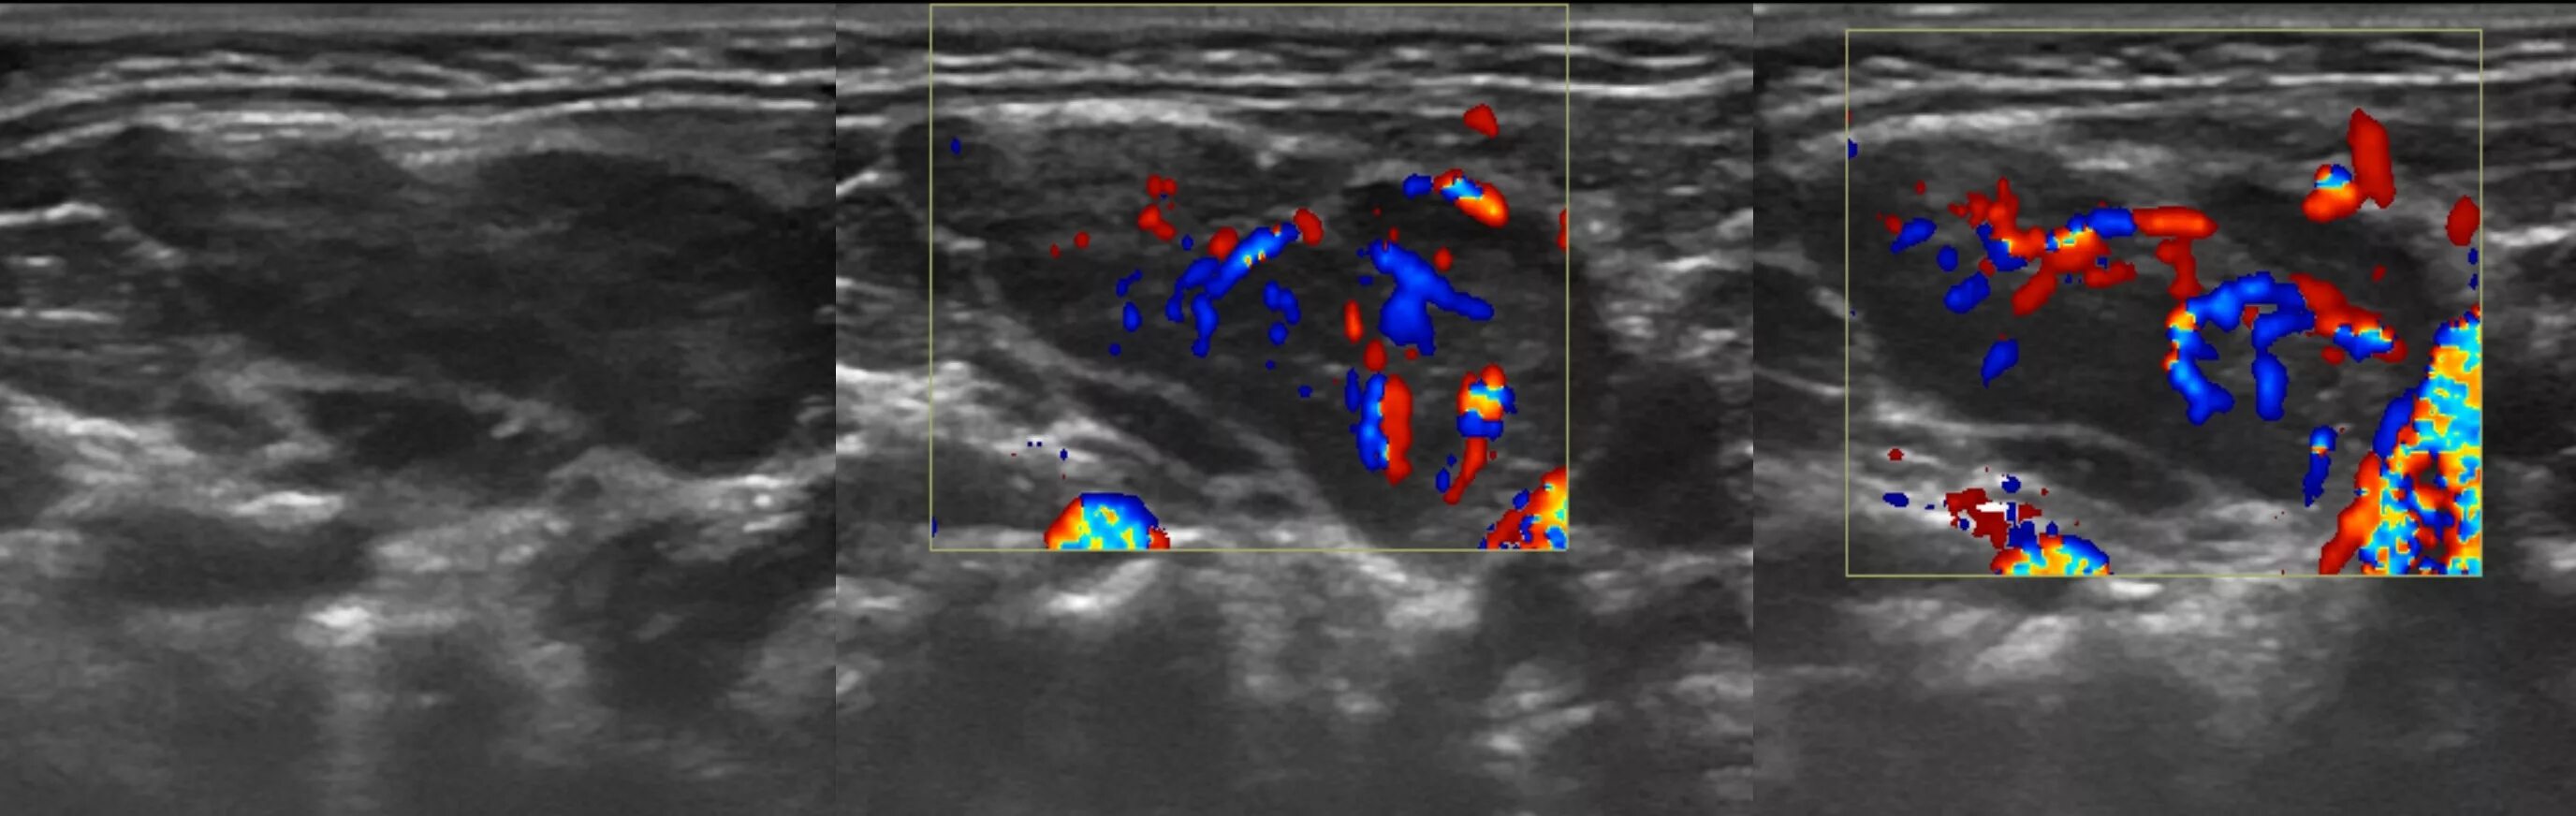

Метастазы в паховых лимфоузлах